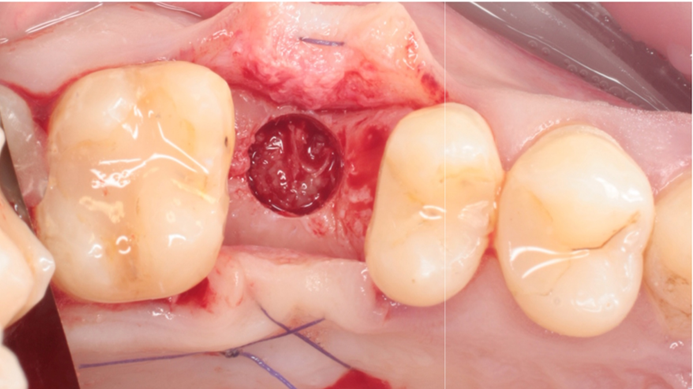

Klinikinis atvejis: Vėlyvoji implantacija: viršutinio žandikaulio ančio dugno elevacija, implanto sriegimas ir kraštinė kaulo regeneracija;

- Dr. Irfan Abas klinikinis atvejis -

Vėlyvoji implantacija, ančio dugno elevacija, ančio dugno elevacija atviru būdu, kraštinė kaulo regeneracija, Dr. Irfan Abas, AnyRidge, MiLA chirurginis rinkinys, kaulo regeneracija;

AnyRidge implantų sistema, MILA chirurginis rinkinys;